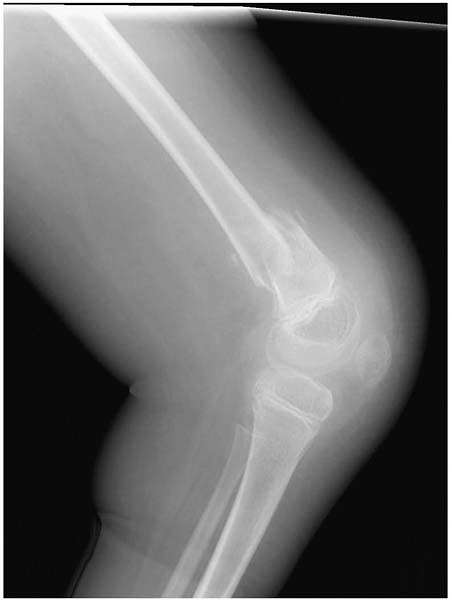

▪ FIGURE 15-3 (A)

This boy with thoracic level spina bifida presented with a chief complaint of (painless) leg swelling. The leg was warm to touch. (B) Radiographs demonstrate copious new bone formation. (C) To make matters even more confusing, when children with spina bifida fracture through the growth plate, there may be no callus formation. Clinically, this young girl with thoracic level spina bifida had motion through the Salter I fracture of the distal femur. |

▪ FIGURE 15-4

Nonambulators with osteopenia frequently have fractures of the distal femoral metaphysis. Have a high index of suspicion when children who were in a hip spica cast for hip surgery present with increasing pain shortly after the spica cast was removed. |